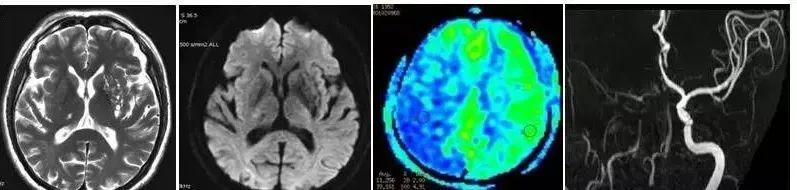

图片ASL显示缺血区域及低灌注区,DWI代表核心梗死区域,ASL-DWI=缺血半暗带

短暂性脑缺血发作:常规T2及弥散图像显示左基底节及右侧丘脑多个小腔隙灶;3D TOF显示右颈内动脉明显狭窄,可见许多侧枝循环血管。3D ASL CBF灌注图上显示右大 脑半球显示为低灌注区,该病例表明3D ASL对灌注血管的流速敏感,因此能敏感发现供血血管异常及灌注代偿状态。